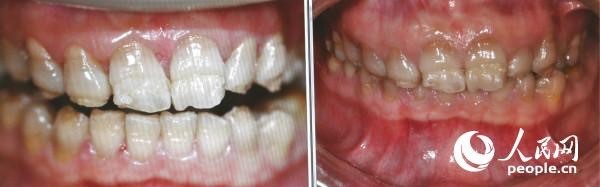

四環(huán)素牙治療前后對(duì)比圖 (人民網(wǎng)記者張希 攝)

人民網(wǎng)北京9月20日電 今天為“全國(guó)愛(ài)牙日”,記者就牙齒健康問(wèn)題采訪了蓋德口腔國(guó)際醫(yī)療中心醫(yī)療總監(jiān)、牙周與美學(xué)修復(fù)專家李秀紅。李醫(yī)生提到,四環(huán)素牙是因?yàn)樗沫h(huán)素進(jìn)入人體之后,分布于各個(gè)器官和組織,被牙齒吸收之后與鈣作用,形成四環(huán)素與鈣的復(fù)合物。牙釉質(zhì)發(fā)育需要鈣質(zhì),而四環(huán)素與鈣結(jié)合會(huì)導(dǎo)致鈣質(zhì)的缺失,這會(huì)導(dǎo)致牙釉質(zhì)發(fā)育不全,俗稱“四環(huán)素牙”。李醫(yī)生介紹,四環(huán)素牙是六七十年代較為常見(jiàn)的疾病,隨著四環(huán)素的使用減少,八、九十年代后四環(huán)素牙少見(jiàn)。四環(huán)素牙由于釉質(zhì)發(fā)育不全,容易磨損,出現(xiàn)深的黃或青、灰的牙本質(zhì)顏色,影響美觀。

如何治療四環(huán)素牙呢?李秀紅介紹說(shuō):“在以前,改善四環(huán)素牙顏色的常見(jiàn)方法是做烤瓷牙。即把病人的牙齒磨小并為其戴上烤瓷牙套,這種方法對(duì)牙齒有一定傷害,甚至?xí)䲟p傷牙神經(jīng),F(xiàn)在四環(huán)素牙可以通過(guò)美白的方法改善顏色問(wèn)題,對(duì)牙齒沒(méi)有傷害,牙齒也不會(huì)出現(xiàn)敏感,疼痛!保▽(shí)習(xí)生李星星)